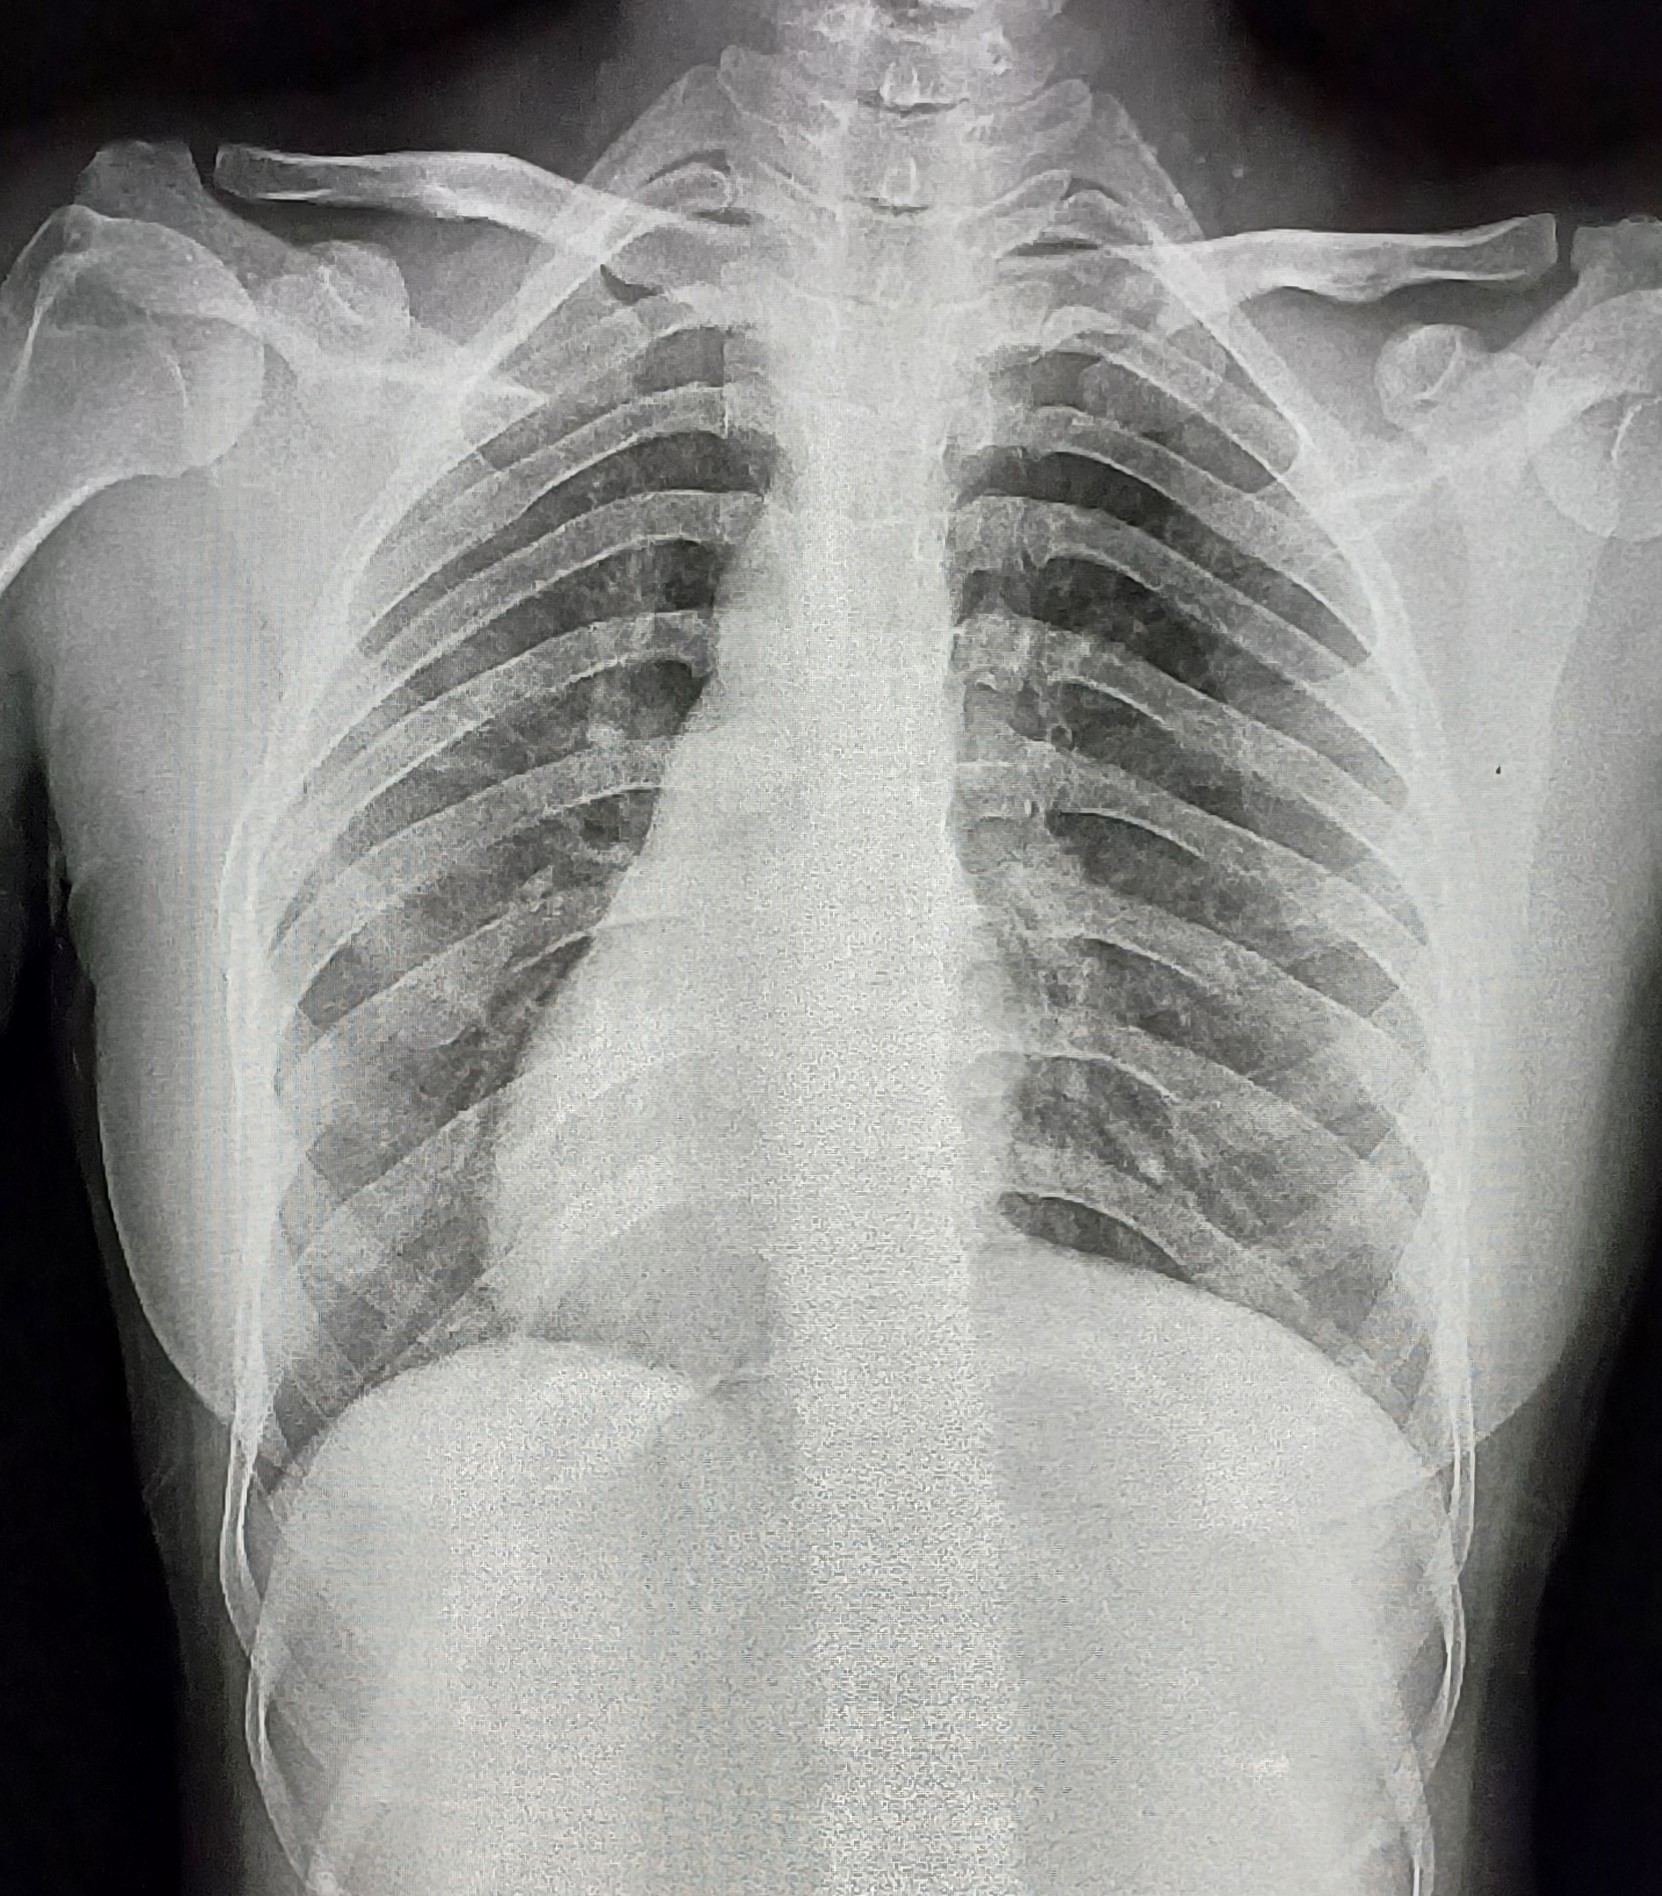

| 5 | IGGMC, Nagpur, Nagpur | P2 | 29-4467 | Meera Gohare | Consent taken on Paper | 64 Yrs. |

Provisional Diag : ?

Final Diag : Disseminated TB (Miliary TB With Abdomen Koch) |

TB Case (Confirmed) | Abnormality visible on x-ray |

View |